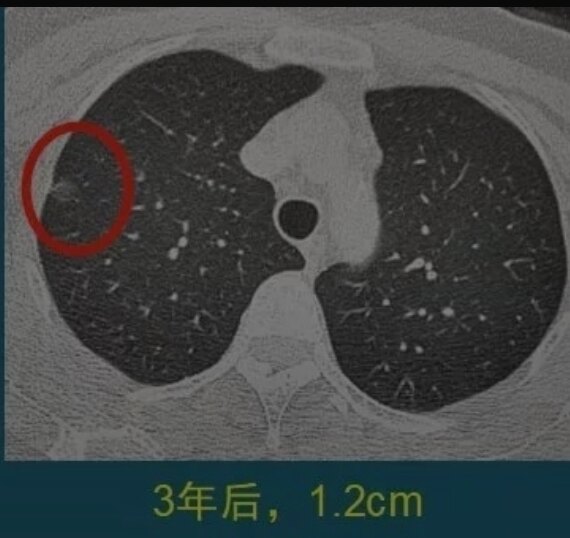

上面两张图是一位中年女士,体检发现右肺纯磨玻璃结节1.1cm,定期复查,3年后好像增大了一点,直径大约1.2cm,边缘出现少量细索条影,她不想再观察了,做了胸腔镜微创手术,病理是原位腺癌。